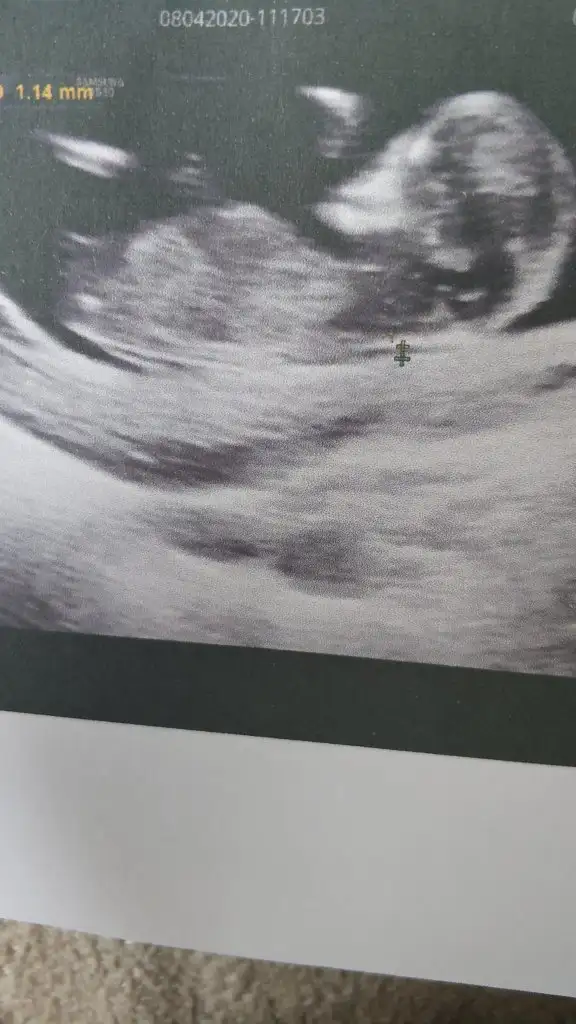

Erkek diyecem emin olamadım net değil nubu 12-13 haftayida paylaşın zaten 10+6 USGIkra meyra tahmin yapar mısın bana da

Evet bugün Kü sonuç bu. Tşk ederimErkek diyecem emin olamadım net değil nubu 12-13 haftayida paylaşın zaten 10+6 USG

Erkek gibi sanki net değil ama dik gibi sankiBende bir tahmin alabilir miyim 11+6 haftalığızdoktor tahminde bulundu bir de sizden alayım :)

Tam bir erkek kafası maşallah doktorunuz erken söylemiş ne dedi merak ettimBende bir tahmin alabilir miyim 11+6 haftalığızdoktor tahminde bulundu bir de sizden alayım :)

Başka yok maalesef doktor erkek gibi dediErkek gibi sanki net değil ama dik gibi sankibaşka USG varsa paylasin

Emin olamadım olmayada bilir erkek diyorum şimdilik tekrar USG paylasinMerhaba. 11+3 olduk bugün. Sürekli hareket etmesinden tam yakalayamadı doktor ama bir tahmininiz var mı? Teşekkürler.